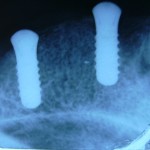

Implanti

Galerija fotografija sa radovima u oblasti zubnih implanta.

Ova galerija sadrži jednu ili više eksplicitnih fotografija sa prikazom medicinskih operacija i ne preporučuju se za osobe koje nemaju odgovarajući stepen tolerancije.